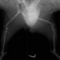

■ 症例20 ポメラニアン 8ヶ月 1.8kg

左右膝蓋骨脱臼 グレードⅢ

2ヶ月前から間欠的跛行が認められ、両膝の膝蓋骨脱臼整復術を行った。

手技は縫工筋及び内側広筋の解放、脛骨粗面の外側転位、滑車ブロック形造溝術、内外側関節包の縫縮を選択し実施した。

右側の膝蓋骨脱臼は上記手技で整復されたものの、左側はそれのみでは膝蓋骨が浮く様子が認められた。その為、PDS縫合糸にて膝蓋靱帯を1糸のみ縫合し、靱帯の縫縮を行った。

膝蓋骨脱臼は膝関節における膝蓋骨の内外側の脱臼と定義されるが、時として単純な内外の脱臼ではなく、膝蓋骨が大きく前方に浮き上がるように脱臼する場合がある。特にトイプードルやポメラニアンといった犬種に多く認められる。

内側脱臼に加えて前方への浮き上がりを矯正する為に、従来より脛骨粗面転移により膝蓋靭帯を外方と下方に引っ張り、固定する方法を選択する。膝蓋骨の前方への浮き上がりが軽度の場合は、従来法ではなく関節包の縫縮で対応していた。しかし、一部の症例で膝蓋骨の動きが悪くなり伸展機構が円滑に機能せずロボット様歩行になるケースがあった。

その為、膝蓋靭帯自体を縫縮する方法を採用した。この方法により、膝関節の伸展機構を妨げず膝蓋骨の軽度の浮きを矯正することが可能となった。

本症例の経過は良好である